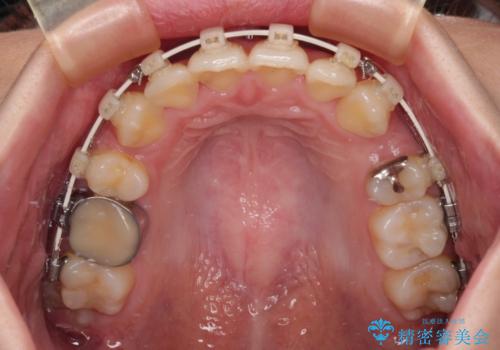

- 矯正装置

- 審美装置

- 八重歯やクロスバイトを気にして来院された患者様です。

口元の突出感はありませんでしたが、デコボコが強く、非抜歯矯正とすると出っ歯仕上がりとなる可能性があったため、上下左右の第一小臼歯4本を抜歯し、ワイヤー装置にて矯正治療を行うこととしました。